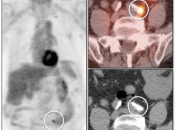

Lung Nodule Identification:

NAC images can occasionally be useful in identifying mild to moderately FDG-avid lung nodules, especially those located in the lung periphery or lung bases.